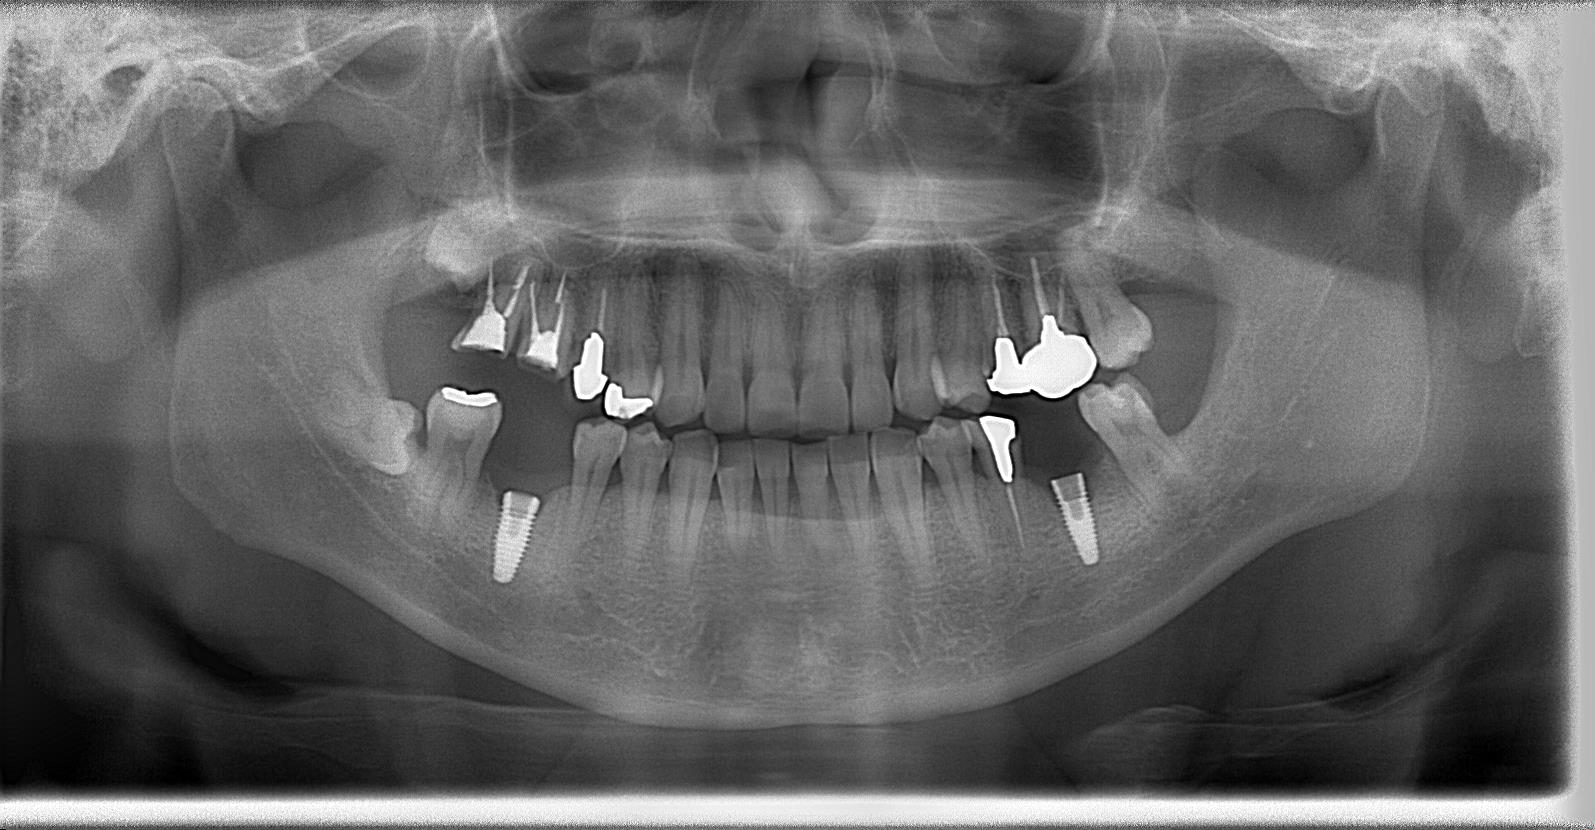

インプラント体1次埋入の術後パノラマレントゲン写真

術中インプラント埋入した状態は良好です。(左下と右下)